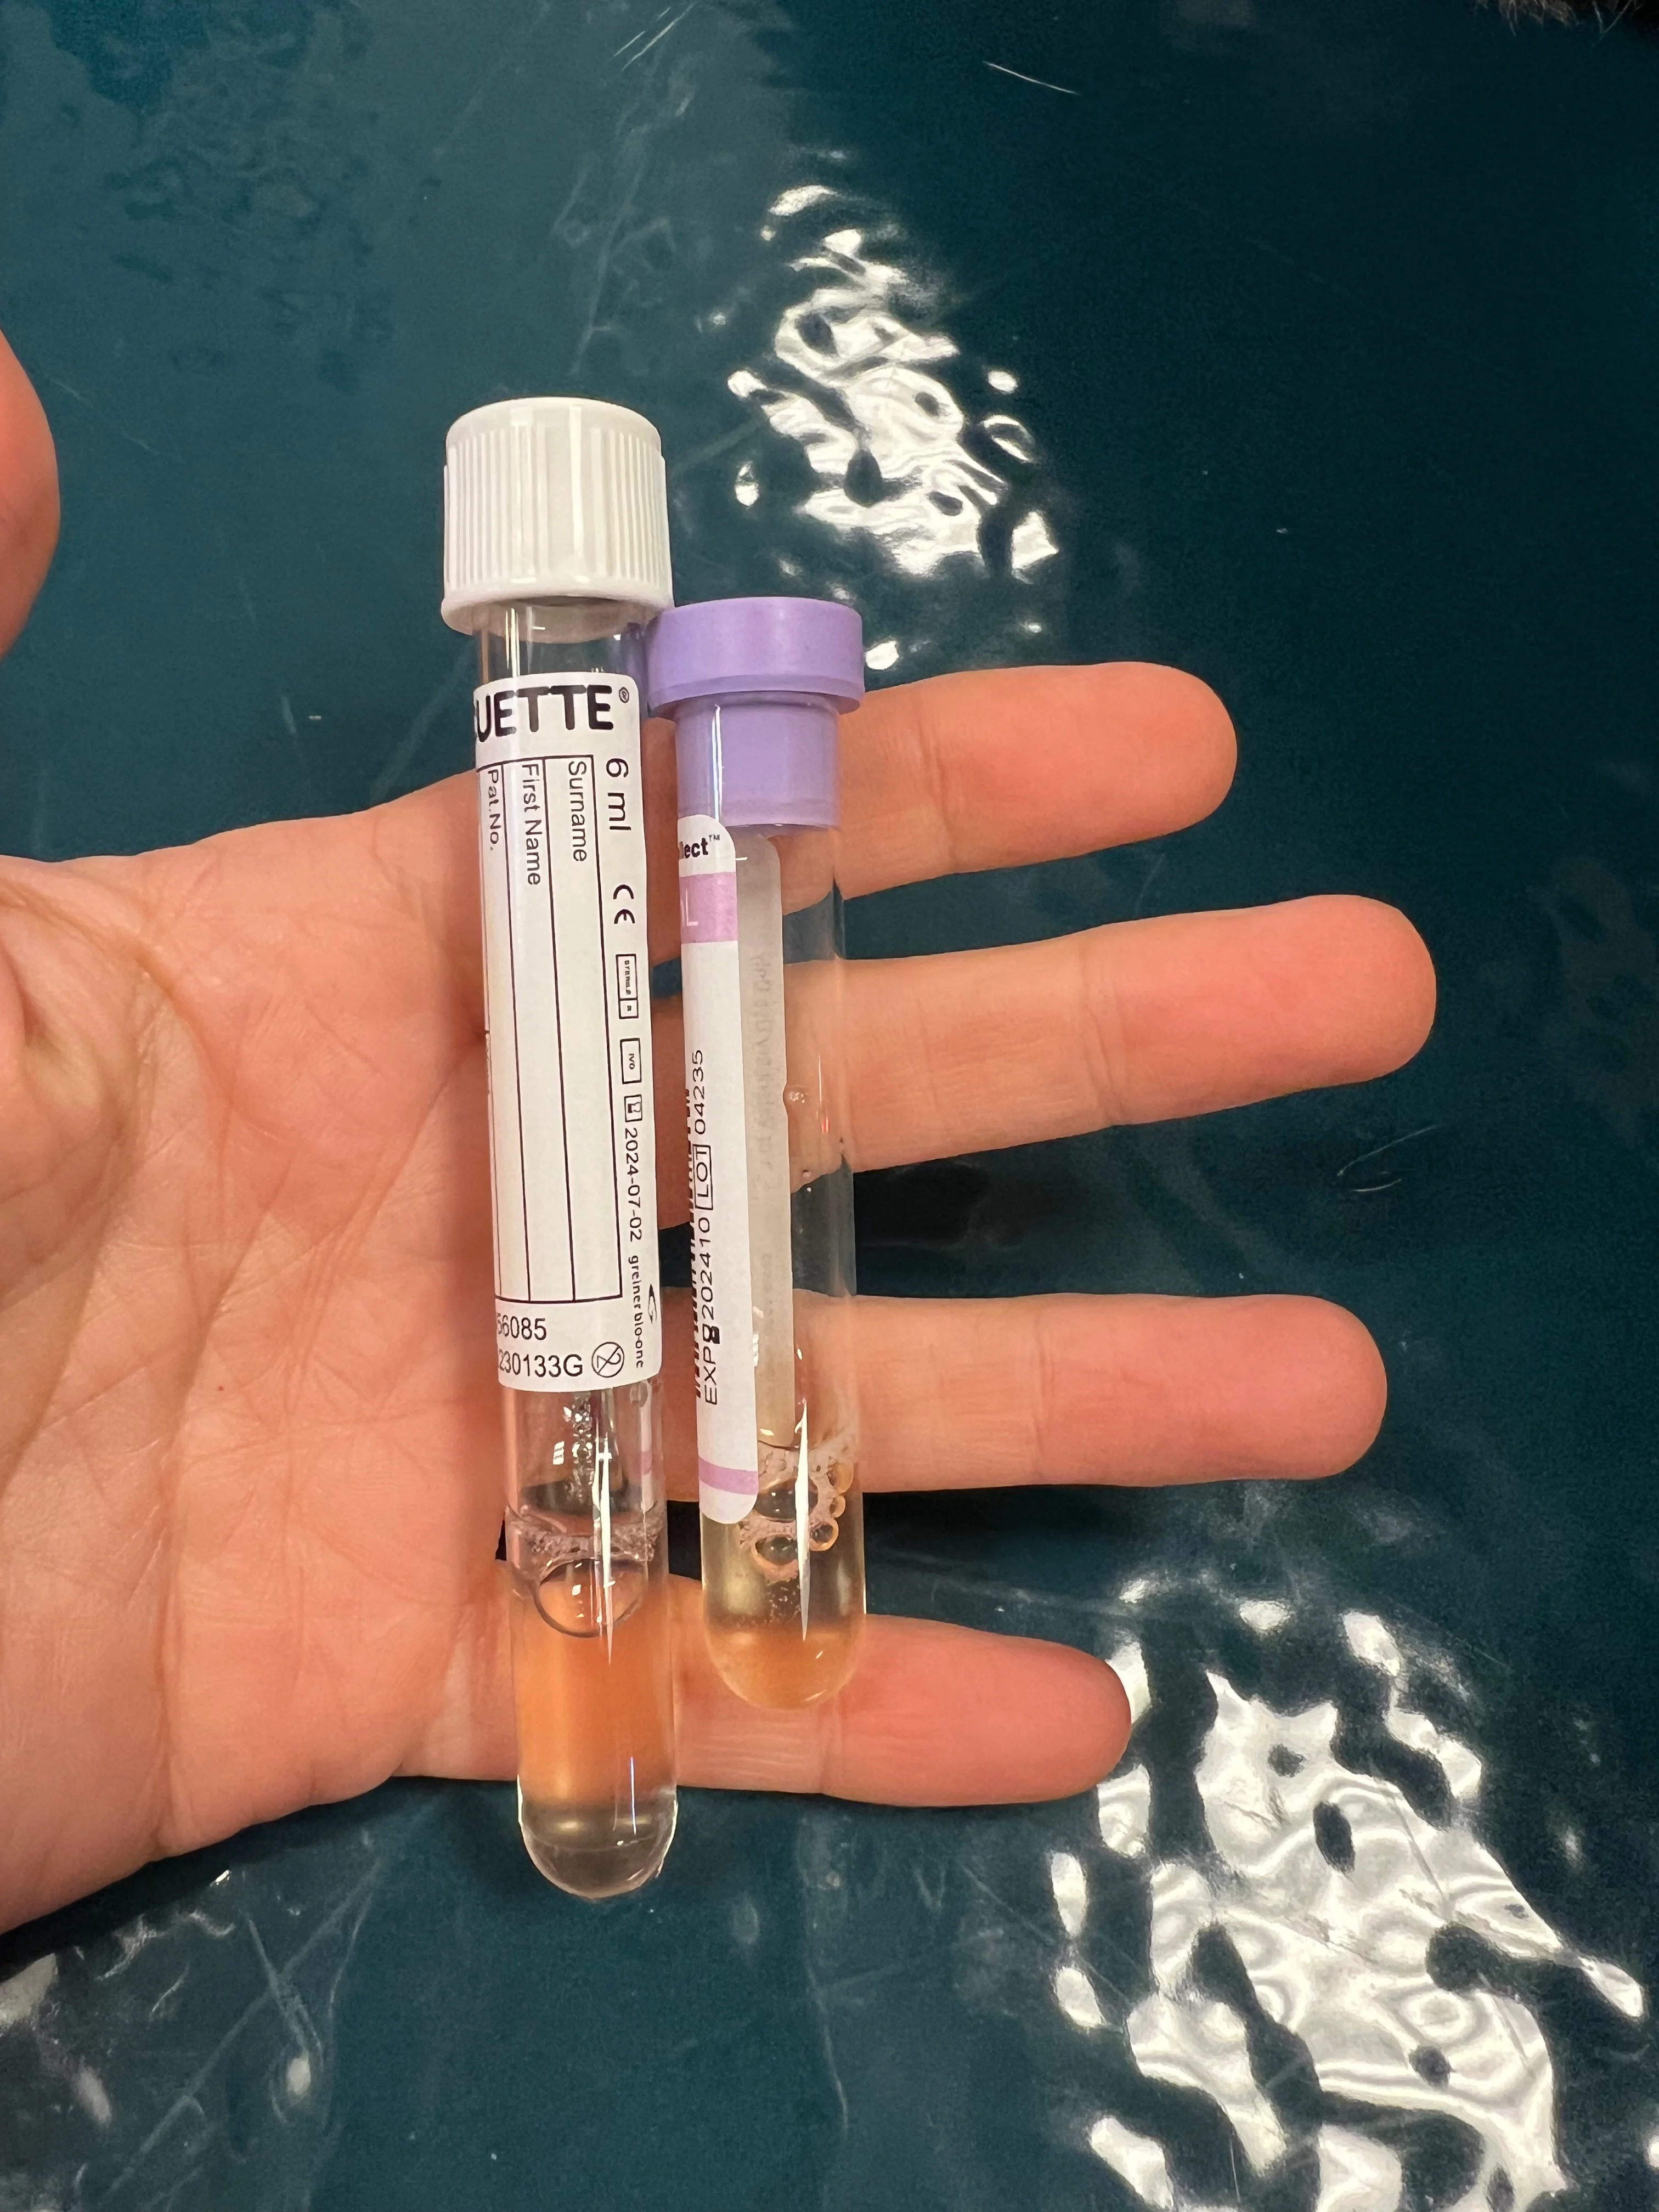

Lavender-top and nonadditive tubes

Turn the stopcock so it is open to the patient. Apply gentle negative pressure to the syringe, and allow fluid to fill the syringe. Once the syringe is full, turn the stopcock off to the patient and open to the collection container for evacuation. Repeat this process until negative pressure is obtained and the pleural effusion is removed. Save samples in lavender-top and nonadditive tubes for analysis. If pyothorax is suspected, also save a fluid sample for culture and susceptibility testing.

Unilateral or bilateral drainage may be required. The volume removed from each hemithorax should be quantified and described.

In cases of hemothorax, small-volume thoracocentesis may be needed. If blood is obtained, a small amount should be placed in a container and observed for clotting. If clots are noted, the procedure should be stopped, the location of fluid reconfirmed via POCUS (if available), and/or the needle repositioned (eg, retapping one intercostal space cranial or caudal to the original site, inserting the needle slightly shallower). Blood can be collected in sterile 60-mL syringes and used for autotransfusion, if appropriate (eg, in patients with trauma or coagulopathy); this should be avoided in patients with septic, contaminated, or neoplastic effusions.